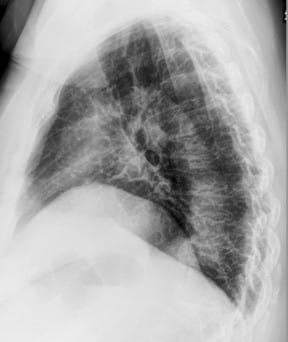

This 67-year old female patient presented to the ER with shortness of breath, in conjunction with chronic pain in her posterior thoracic region upon taking a large breath in. The reading radiologist noticed a suspicious mass-like opacity in the Lateral view. The radiologist stated that, thanks to the DE images, they could they tell the opacity wasn’t a lung mass, but instead far less concerning bony outcroppings from the thoracic vertebrae.